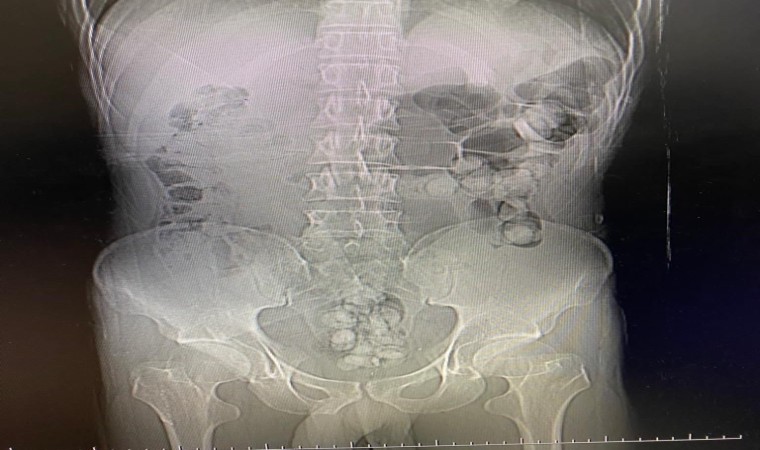

Erzurum Emniyet Müdürlüğü tarafından yapılan açıklamada şöyle denildi, “Erzurum Emniyet Müdürlüğü Narkotik Suçlarla Mücadele Şube Müdürlüğümüzce narkotik madde ile mücadele kapsamında batı illerine uyuşturucu madde nakli yapan şahıs ve araçlara yönelik 20.07.2023 tarihinde Erzurum-Erzincan karayolu üzerinde İran’dan ülkemize giriş yapan yolcu otobüsü durdurulmuş, otobüs içerisinde bulunan yabancı uyruklu şahsın yapılan üst aramasında meyve suyu kutusuna gizlenmiş vaziyette 36 parça halinde toplamda 245,43 gram Afyon Sakızı, yapılan iç beden muayenesinde mide ve bağırsak kısımlarında uyuşturucu madde olduğu tespit edilerek 27 parça halinde 192,69 gram Afyon Sakızı çıkarılmış, şahıstan toplamda 63 parça halinde 438,12 gram Afyon Sakızı ele geçirilmiş, otobüste bulunan Morteza Cheshm B. isimli yabancı uyruklu şahıs gözaltına alınmış, sevk edildiği adli makamlarca tutuklanarak cezaevine teslim edilmiştir.”